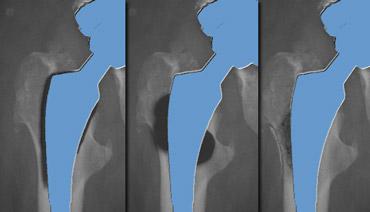

Non Cemented THA

Việc cấy ghép khớp háng không xi măng dạng xốp (bone ingrowth prosthesis) dẫn đến sự thay đổi phân bố ứng suất lên xương tự nhiên, đặc biệt ở các mẫu cũ hơn với cán khớp háng không thuôn và được phủ hoàn toàn.

Hiện tượng che chắn ứng suất (stress shielding) ở vùng gần có thể dẫn đến loãng xương vùng gần và tiêu xương calcar.

Tải trọng ứng suất ở vùng xa có thể dẫn đến dày vỏ xương và xơ cứng bắc cầu tại đầu mút của khớp giả (gọi là bệ đỡ – pedestal).

Để tránh những thay đổi này, hầu hết các khớp giả không xi măng hiện đại chỉ có cố định ở vùng gần, do đó thường không thấy hiện tượng che chắn ứng suất vùng gần.

Phần xa của khớp giả xương đùi không bị ‘chịu tải’, do đó sẽ không có hiện tượng tải trọng ứng suất vùng xa.

Trong các trường hợp thay khớp háng không xi măng ổn định, các vùng thấu quang tại giao diện kim loại-xương có thể xuất hiện, do thông thường sự kết hợp giữa sự phát triển xương vào và sự phát triển mô xơ vào cung cấp sự cố định trong hầu hết các trường hợp.

Mô xơ này biểu hiện dưới dạng vùng thấu quang tại giao diện.

Một lần nữa, vùng này phải ổn định và nằm trong khoảng 1 – 2 mm.

Hình bên trái tóm tắt tất cả các phát hiện ở một số khớp giả không xi măng, có thể là bình thường.

Vùng thấu quang mỏng dọc theo ranh giới xương-kim loại do mô xơ là hiện tượng thường gặp (80%).

Chúng phải nhỏ hơn 2mm và đi kèm với một đường xơ cứng song song với nó.

Nếu chúng ổn định trong 2 năm thì sự cố định bởi mô xơ chắc đã xảy ra.

Che chắn ứng suất hay tiêu xương được thấy ở những vùng tương đối không chịu lực.

Các lực được truyền qua thân xương đùi tương đối cứng và biểu hiện là loãng xương ở vùng xương đùi gần với mỏng vỏ xương và tiêu xương cổ xương đùi.

Điều này được thấy ở phía trong là tiêu xương calcar, do calcar đã mất chức năng của nó (hình).

Nó còn được gọi là làm tròn calcar.